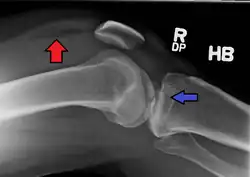

| A severe tibial plateau fracture with an associated fibular head fracture | |